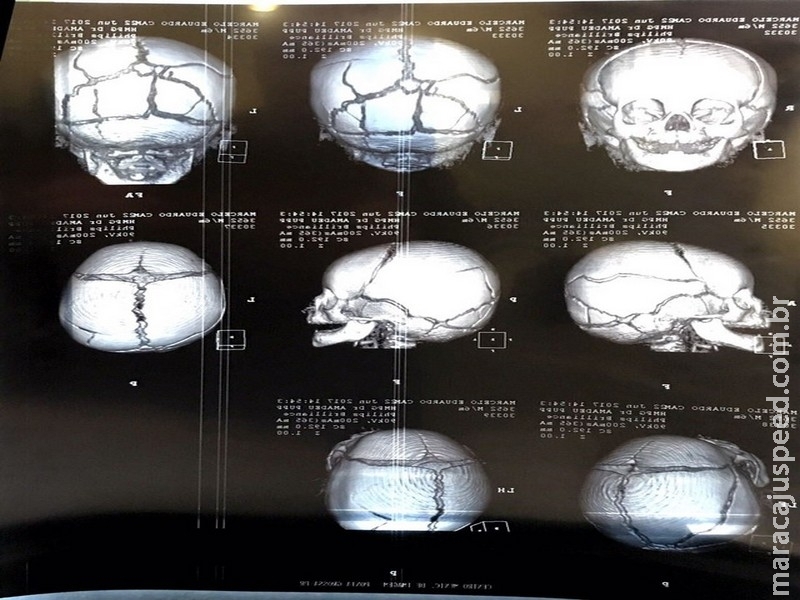

O menino foi levado ao Hospital da Criança em estado grave na semana passada, com várias fraturas no crânio. Na noite desta quinta, ele foi encaminhado para a UTI do Hospital Universitário de Ponta Grossa. Veja a nota dos médicos no final da reportagem.

Segundo a Polícia Civil, o pai foi autuado pelo crime de tortura porque além de múltiplas lesões no crânio, o que indica lesões causadas recentemente, a criança apresentava sinais de mordidas no braço direito, fratura em uma costela e hematomas nas pernas.

- O paciente foi submetido a Tomografia Computadorizada e demais exames indicados. Está sendo acompanhado pelas equipes de Neurocirurgia e de Terapia Intensiva Pediátrica, sendo manejado com tratamento clínico.